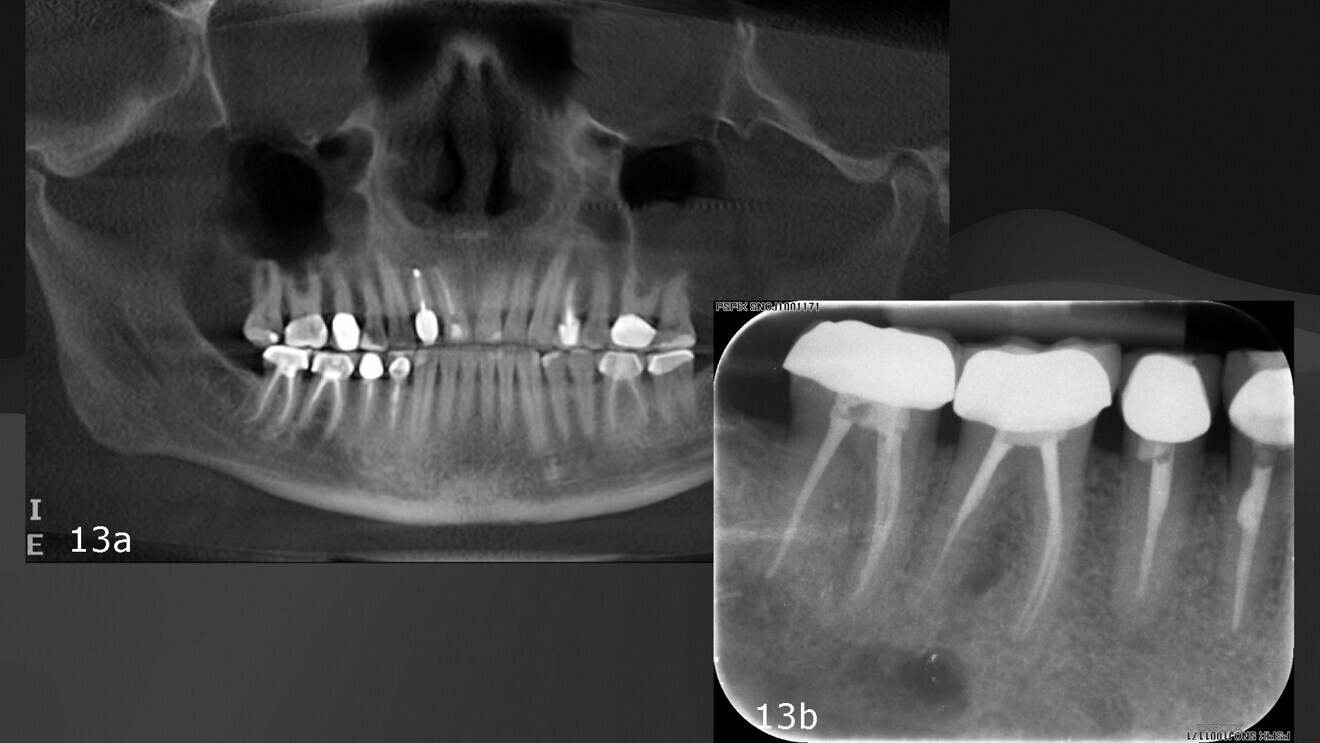

Figs. 13a & b: Panoramic and periapical follow-up images showing a radiolucency under the mandibular right first molar.

The patient in this case was referred back to check on a retreatment performed some years before. It was clear from the radiographs that the periapical area of the molar was not healthy (Figs. 13a & b). A CBCT scan was taken and, when studied in DTX software, showed a lesion under the molar (Figs. 14a–d). After a careful study of the case, it was determined that the lesion was unrelated to the apices, the periodontal ligament was not interrupted and the lesion had no clear epithelial lining. In order to establish the aetiology, the patient was asked about pain on chewing, but reported no discomfort whatsoever. He had also not been involved in a fight, but recalled having slipped when taking a shower and having hit his mandible on the bathtub.